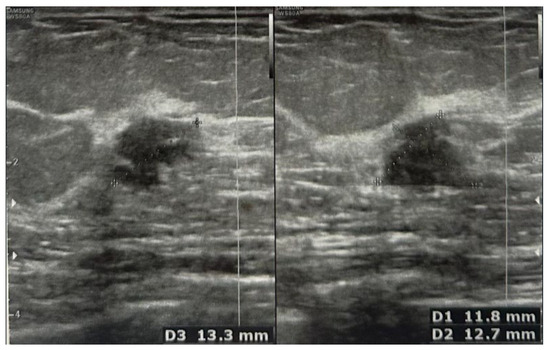

Eight years later, in May 2023, she presented her annual imagistic report where the following was described: abdomen and pelvic MRI—para-aortic left adenopathies with conglomerate aspect, the biggest measuring maximum 23/20 mm and 12/10 mm with features highly suggestive of an oncological process; breast ultrasound and MRI—right breast, supero-external quadrant, hour 10, at approximately 5 cm distance from the mammary papilla, the presence of a hypoechogenic nodule with microcalcifications, irregular margins, measuring 1.33/1.18/1.27 cm (Figure 1 and Figure 2).

Figure 1. MRI image showing right breast nodule (arrow).